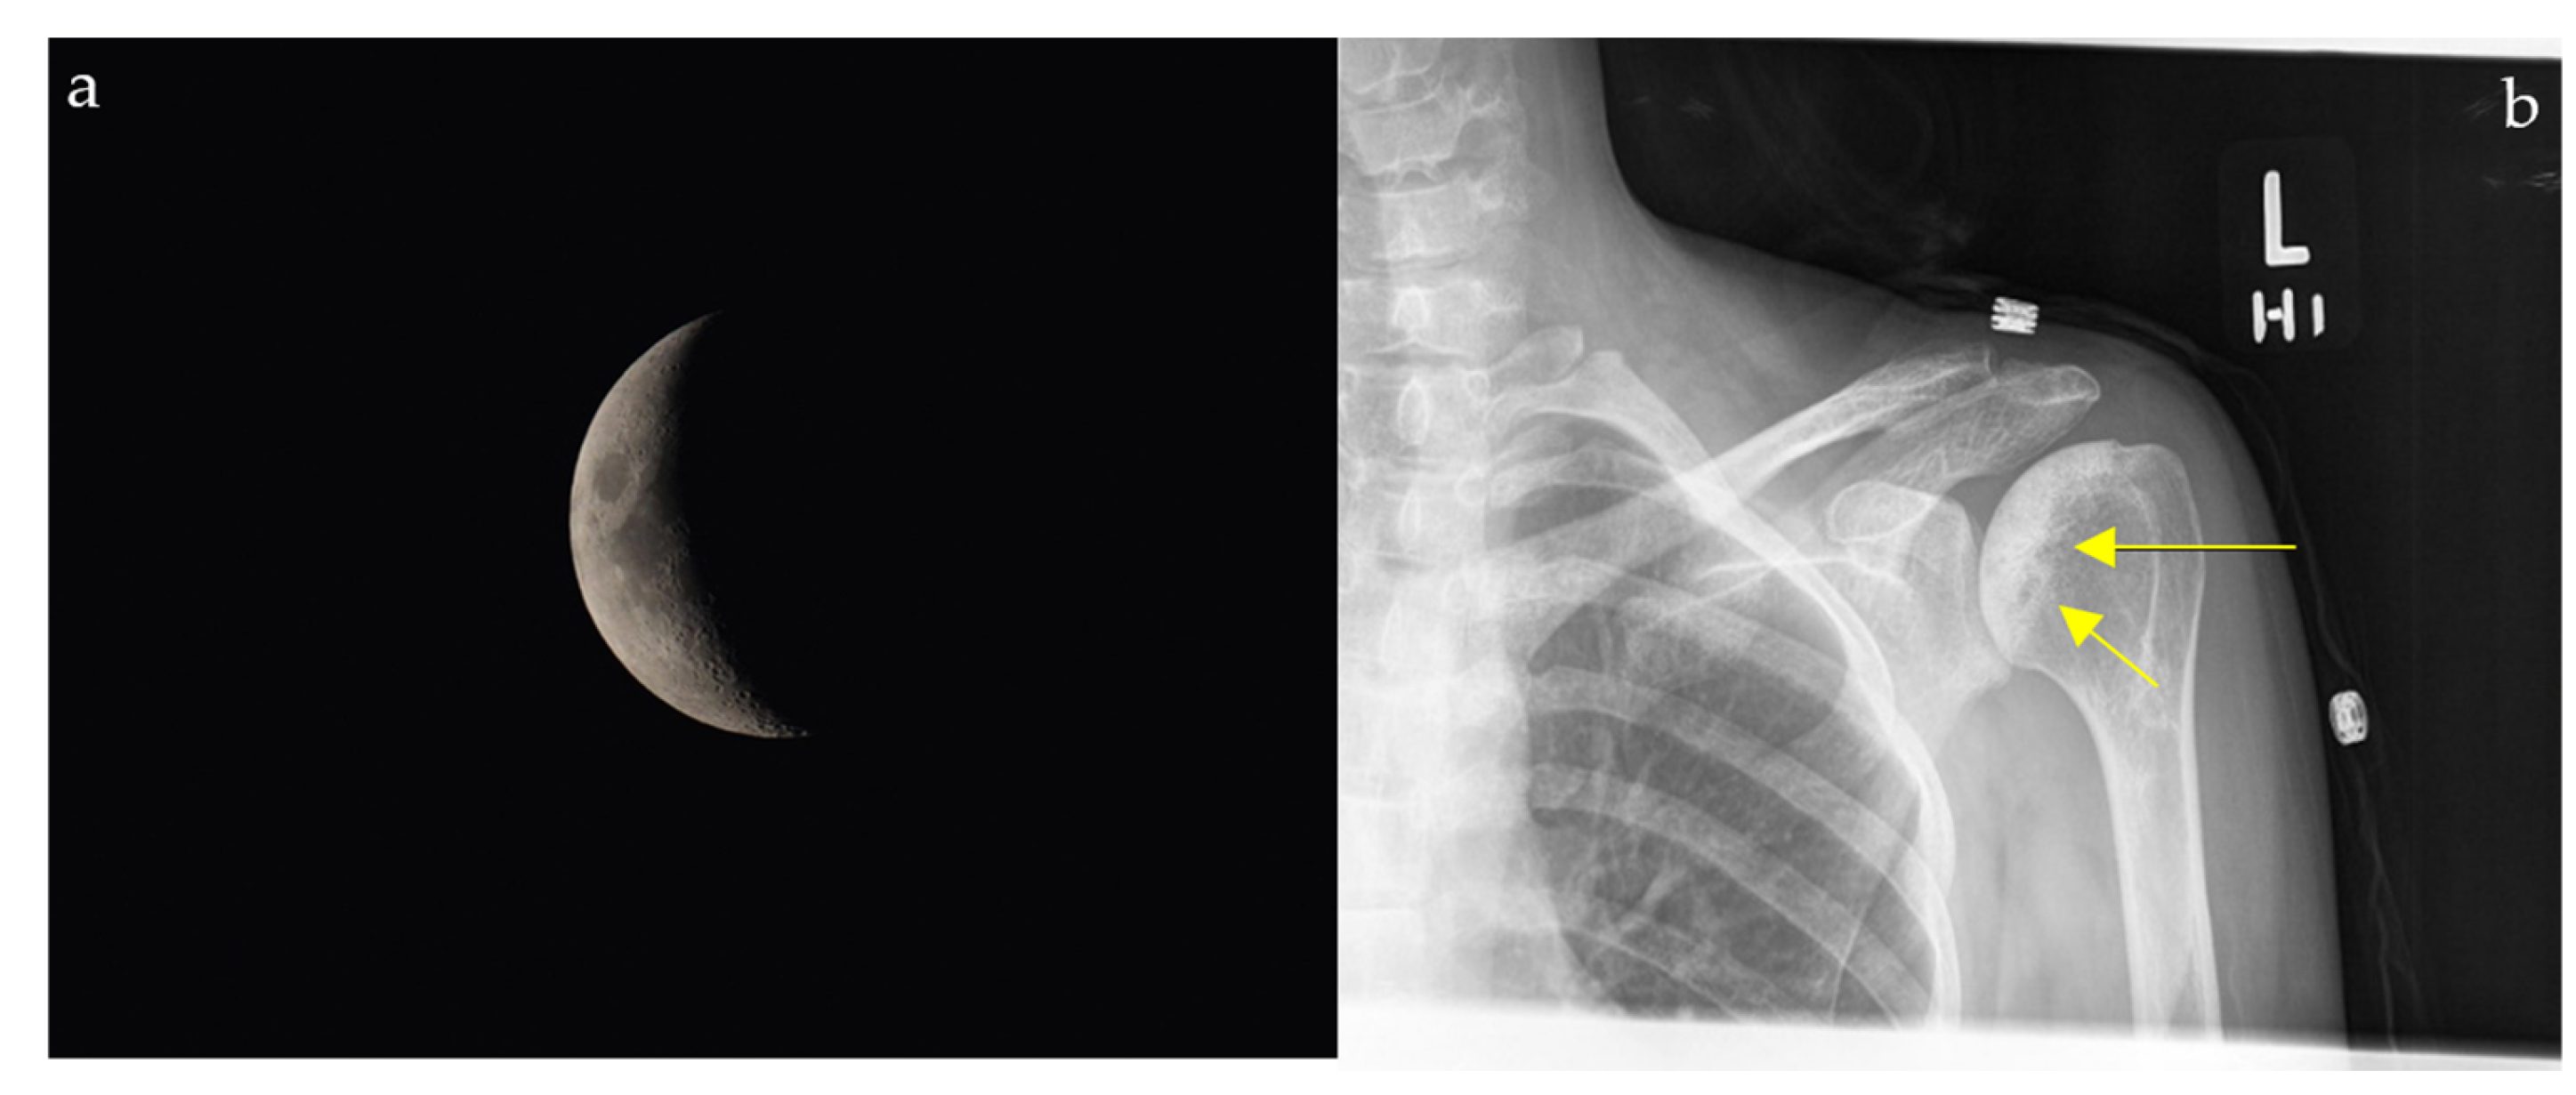

2.4. Loss of Half-Moon Overlap Sign

2.11.2. On Conventional Radiographs